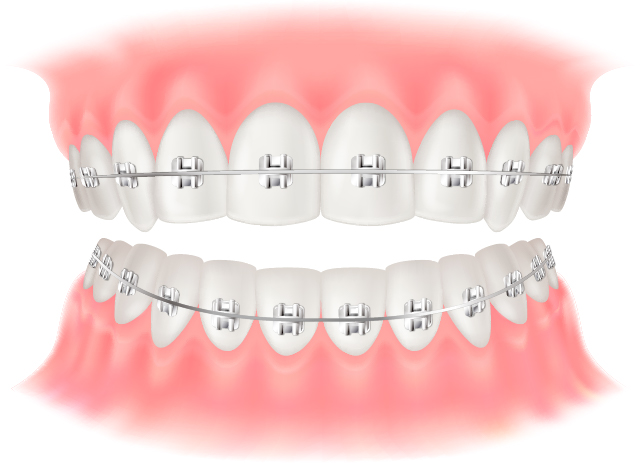

マルチブラケット(金属)

矯正歯科治療で最もよく使用される、マルチブラケットと呼ばれる装置です。